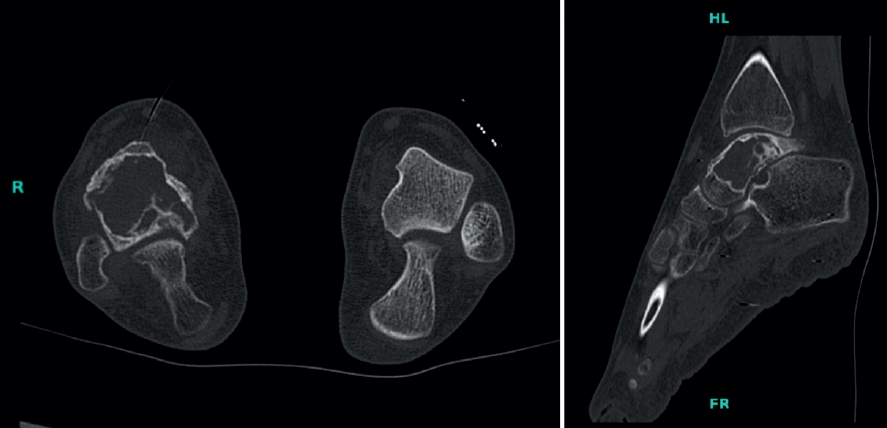

Figura 1. Imagen de rayos X donde se evidencia una lesión con matriz mixta, que ocupa toda la extensión del astrágalo.

Se trata de RSO, de 13 años de edad, que acude a la consulta de ortopedia pediátrica con un cuadro clínico de 1 año de evolución caracterizado por dolor y limitación funcional en el tobillo, según lo que refiere posterior a sufrir una torcedura. Al examen físico se evidencia aumento de volumen, dolor a la palpación en el tobillo y arcos de movimiento limitados. Se realizan imágenes de rayos X donde se evidencia una lesión con matriz mixta, que ocupa toda la extensión del astrágalo (Figura 1). En la tomografía computarizada (TC) del pie se evidencia lesión que compromete el astrágalo, aparentemente insuflativa, sin niveles dentro de la lesión, que compromete los 4/5 posteriores del astrágalo y con bordes escleróticos festoneados (Figura 2). Como parte del protocolo de tumores óseos, se realiza una gammagrafía con tecnecio 99 que informa hipercaptación en el astrágalo y el tobillo (Figura 3). Cuenta con exámenes de laboratorios que informan: hemograma dentro de parámetros normales, fosfatasa alcalina de 147 mg/dL y deshidrogenasa láctica de 150 U/L.